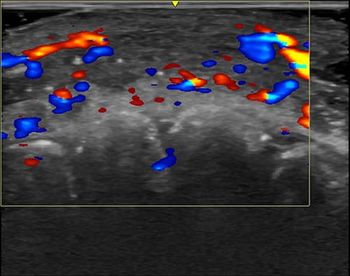

In diagnostic ultrasound, Aloka has been cleared to market two new products. The SSD-5000, cleared Aug. 29, is a variation of the company’s SSD-5500. The new system may be fitted with any of 23 different transducers. The SSD-1000, cleared Aug. 30, is similar to the SSD-1400. The new product can be configured with up to 18 transducers.

Ultrasound

- EUB ultrasound scanner/Sonoprobe (Hitachi Medical Corporation of America, Aug. 10). The product consists of two separate assemblies: the Hitachi EUB-525/EUB-2000 and Fujinon SP711 Sonoprobe system, an optional add-on that allows the two imaging systems to utilize Fujinon probes. The intended use is for endoscopic observation of the GI tract and biliary system.

- GE Logiq 100 Pro (GE Medical Systems, Aug. 23). The new system is an enhanced version of the GE Logiq Alpha 100. The portable general-purpose system consists of a hand-carried console weighing about 22 pounds. The black-and-white system is capable of real-time B- and M-mode imaging with linear and curved-linear array transducers.

- Basic 1, Basic 2, Basic 3 (Atys Medical, Aug.10). The vascular test system is based on the use of peripheral Doppler integrated with photo- and pneumoplethysmography. The system is designed to assist in detecting peripheral vascular disease, both arterial and venous.